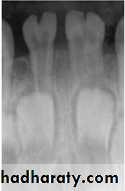

Radiographically:

Roots are extremely short.

Pulps almost completely obliterated.

Periapical radiolucencies:

granulomas

cysts

chronic abscesses

Type I (Radicular Type)

Dentin dysplasia, type I. panoramic & periapical films of the same case show the short and poorly developed roots, obliterated pulp chambers and root canals, and periapical inflammatory lesions.